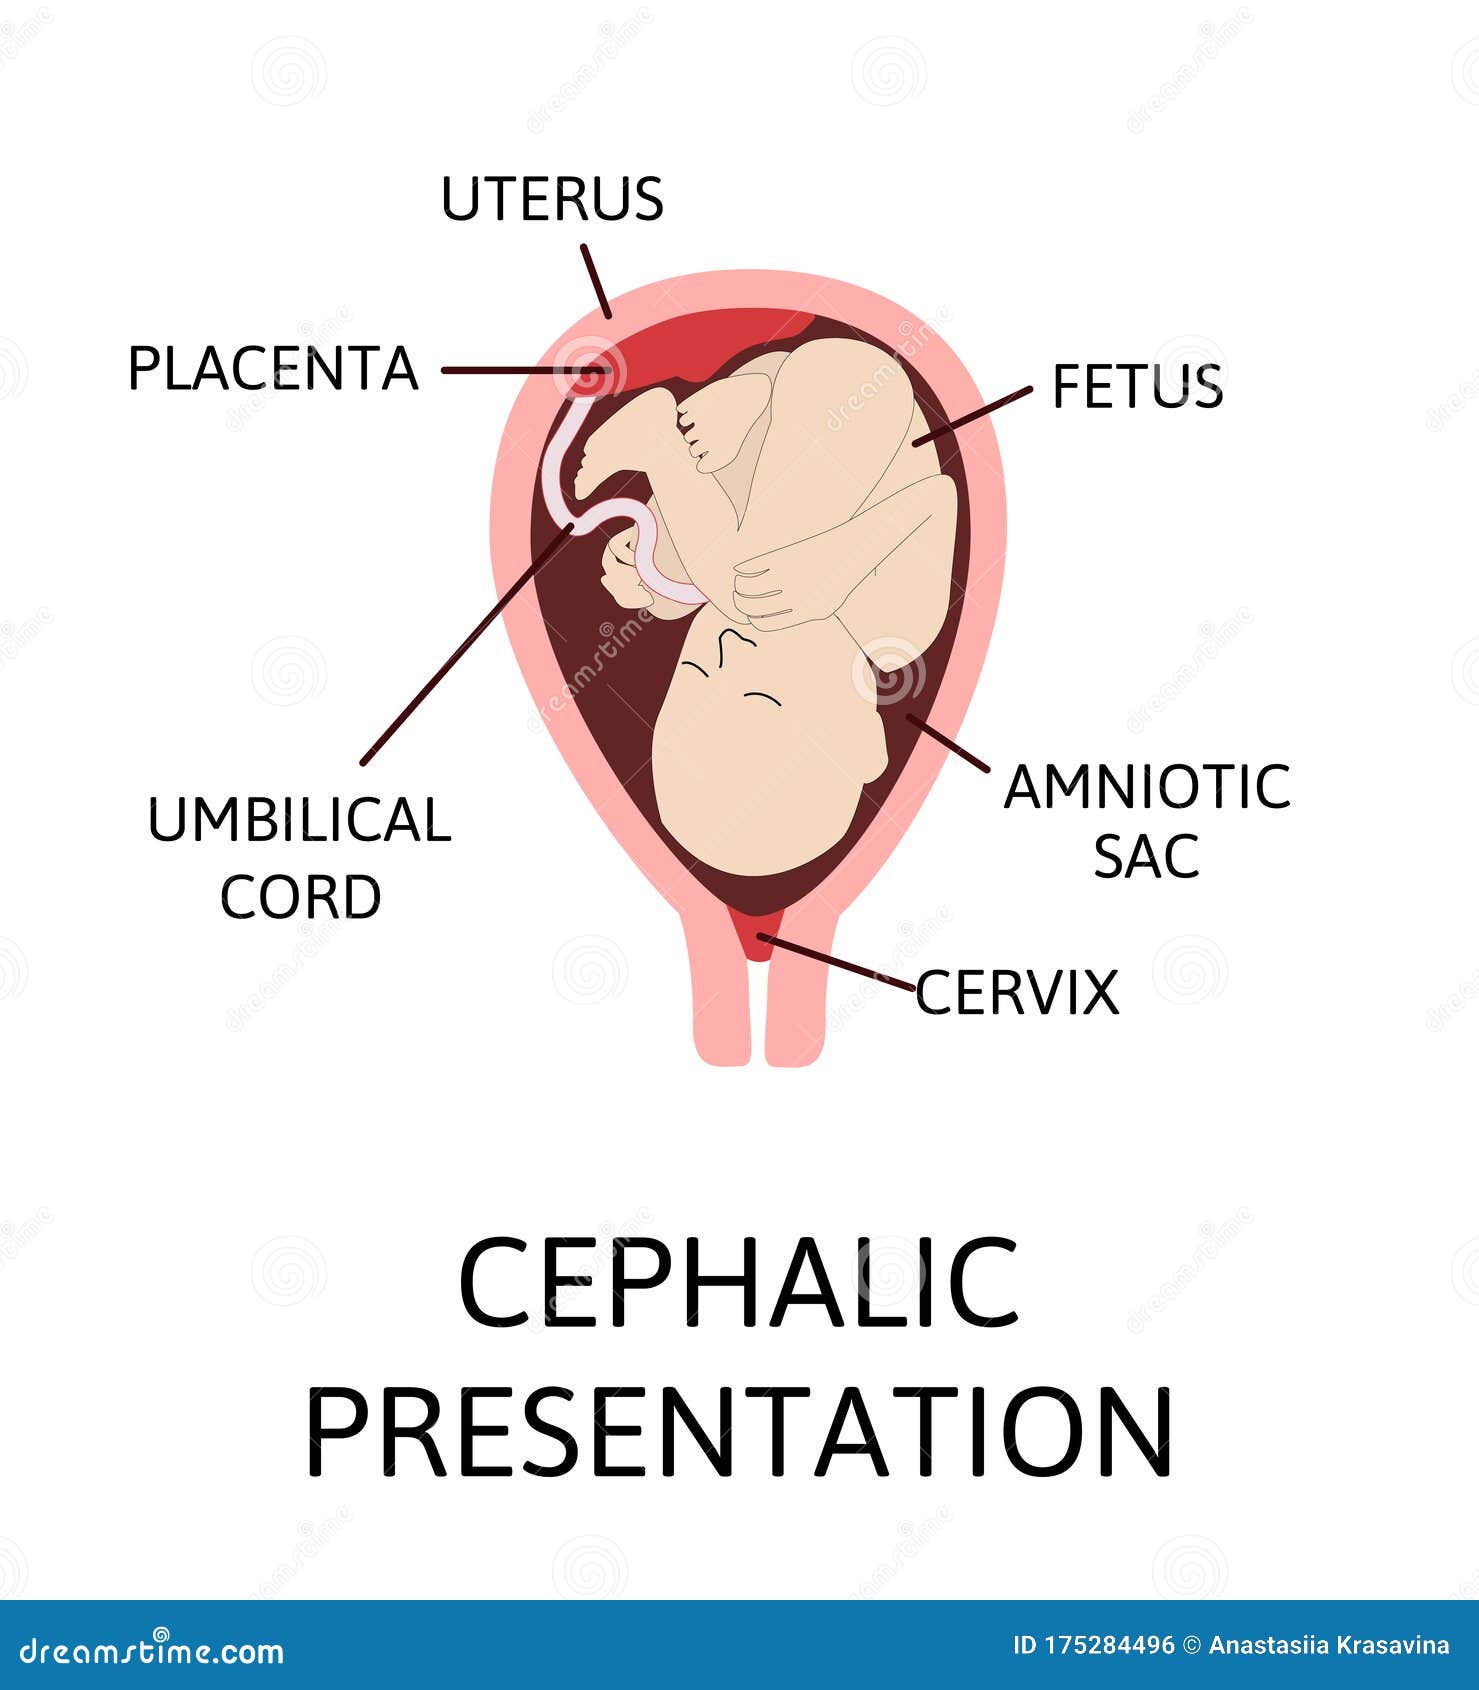

Fully Labeled Diagram Of Fetus Developing In The Uterus Stock

https://st2.depositphotos.com/1293234/8821/v/950/depositphotos_88210764-stock-illustration-fully-labeled-diagram-of-fetus.jpg

https://thumbs.dreamstime.com/z/different-baby-positions-uterus-pregnancy-different-baby-positions-uterus-pregnancy-cephalic-breech-175284496.jpg